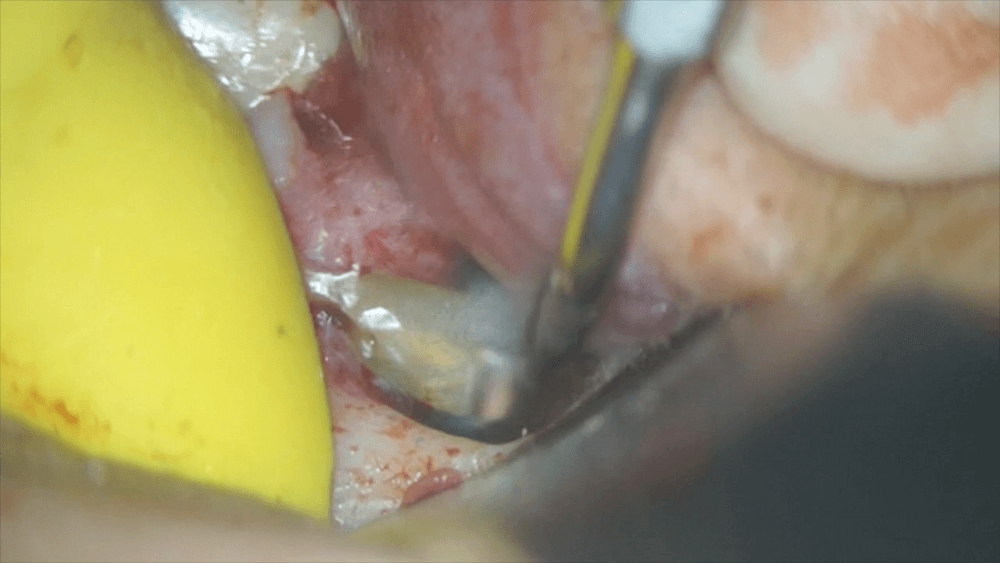

マイクロスコープを用いて、処置を行います。まずは、根の先をカットします。と、同時に歯石も取り除きます。

そして、その他に汚れの取り残しがないか、確認します。

取り残した汚れがないことを確認したら、今度は、根の先から、薬をつめるための器作りを行います。

その器の中に、MTAセメントと呼ばれる材料を入れます。